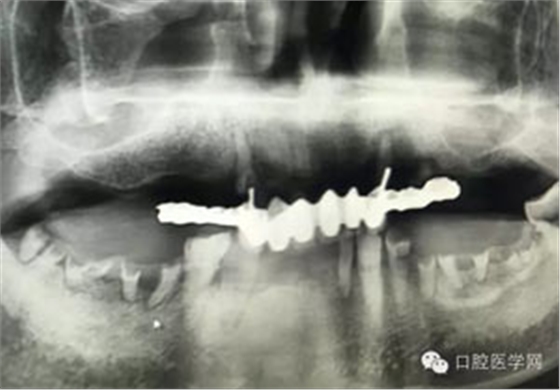

病例1:患者迫切希望保留自己的這一顆牙齒,根尖周陰影比較大,二度松動(dòng).而且旁邊有種植修復(fù)體,和患者溝通好后,治療好后觀察一個(gè)月后冠修復(fù),因?yàn)橛蟹N植的后期修復(fù),所以有了機(jī)會(huì)觀察,術(shù)后三個(gè)月和術(shù)后四個(gè)月,根尖恢復(fù)的還算不錯(cuò),希望能夠繼續(xù)觀察下去.這樣子的病例,做的時(shí)候我們一定要非常的小心,和患者要有充分的溝通以及不同科室的溝通然后決定怎么樣做比較好,假如就是出現(xiàn)了問(wèn)題,到時(shí)候我們也比較好處理些,免得我們自己到時(shí)候不好收?qǐng)觥?/span> 病例2:364647中齲的樹(shù)脂充填,現(xiàn)在樹(shù)脂的充填材料非常之多,有些時(shí)候,我們感覺(jué)有了好的材料我們就可以做出好的修復(fù),可是這是在我們有扎實(shí)的基本功的基礎(chǔ)上的,我們可以沒(méi)有那么好的樹(shù)脂,那么多的顏色選擇,修復(fù)的那么的逼真,但是我們至少要恢復(fù)患者牙齒的功能,將腐質(zhì)去除干凈,薄壁弱尖消除掉,選擇好適應(yīng)癥,給患者以盡可能好的修復(fù)。 來(lái)源于KQ88